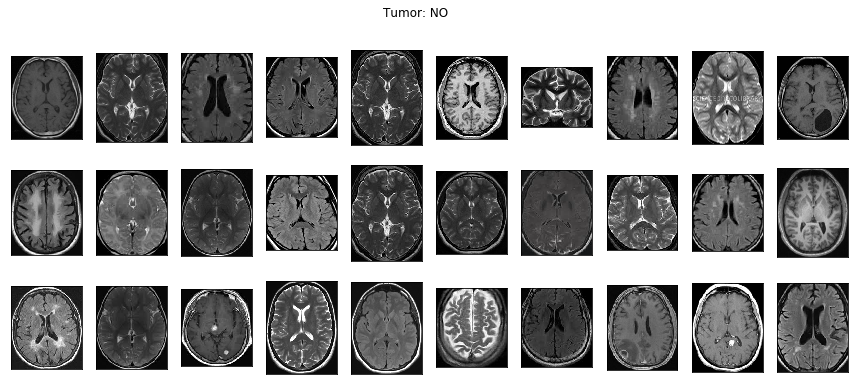

下記画像を見れば分かるように、ここで提供されているデータセットの画像はサイズがバラバラで、しかも脳の周りの黒い空白スペースの面積もバラバラです。

モデルに変な学習をさせないためにも、画像ごとの差はできるだけ小さい方が望ましいので脳の周りの余計な部分は削除します。

上記で不要な部分を削除すると、下記のように画像に統一感が出てきます。